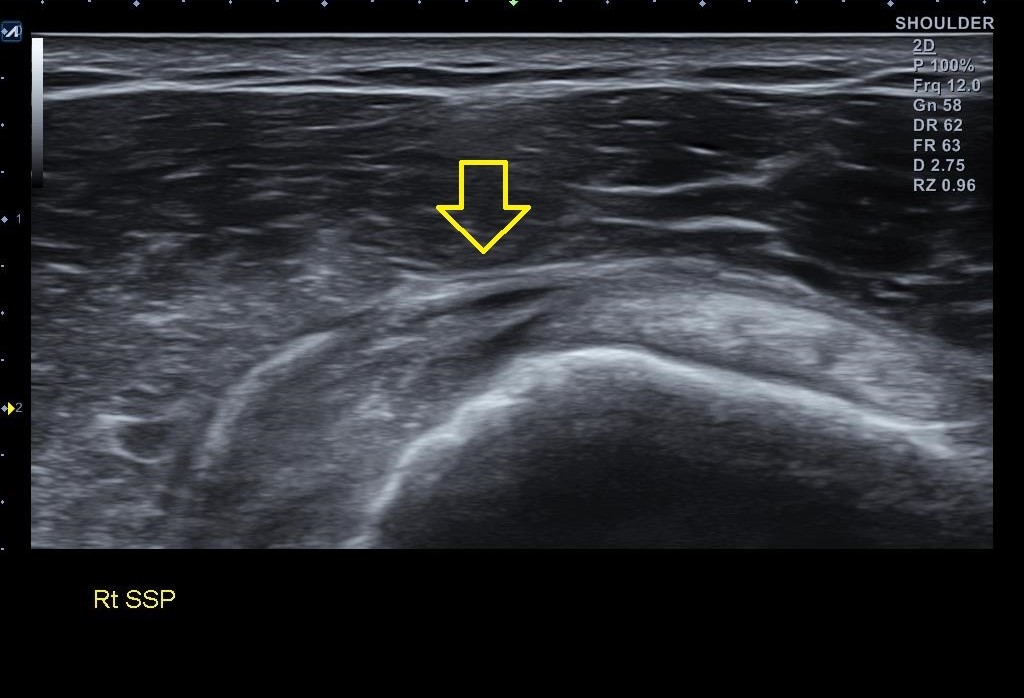

골극이 보이는 상완골 대결절 부위는 극상근 힘줄의 부착부위입니다. x-ray상에 이상 소견이 보인다는건 극상근 힘줄에도 문제가 있을 가능성이 높다는 이야기죠. 힘줄 상태를 확인하기 위해 초음파 검사를 진행했습니다. 결과는...

나 : 초음파 검사 결과를 보니까.... 회전근개 중 극상근이라는 힘줄 파열이네요.

나 : 네 단순 염증 정도 아니구요... 힘줄 파열입니다.

나 : 초음파 검사상 파열 범위와 길이가 아주 심하진 않아서 우선 보존적 치료를 좀 해보고 4주 간격으로 초음파 검사를 몇번 해보면서 지켜봐야 할거 같네요. 지금보다 심해지면 MRI 촬영이 필요할 수 있습니다.